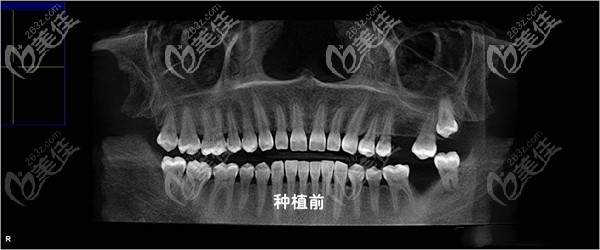

术前照片:

但在去年洗牙时,就发现缺失牙旁边的牙齿已经开始倾斜,本身自己爱抽烟又再加上牙齿缺失,整个口腔环境其实一直都不好,所以,在两个月前我决定来杭州北乐口腔做了瑞士ITI种植牙。

种植牙一般分为三个步骤,先是种上种植体,之后过三个月再来安装基台之后再是牙冠,而我现在是先植入了种植体。

给大家看看我植入植体后,整体感受还是不错的,医生技术也比较娴熟,术中也打了麻醉,没有明显不适。